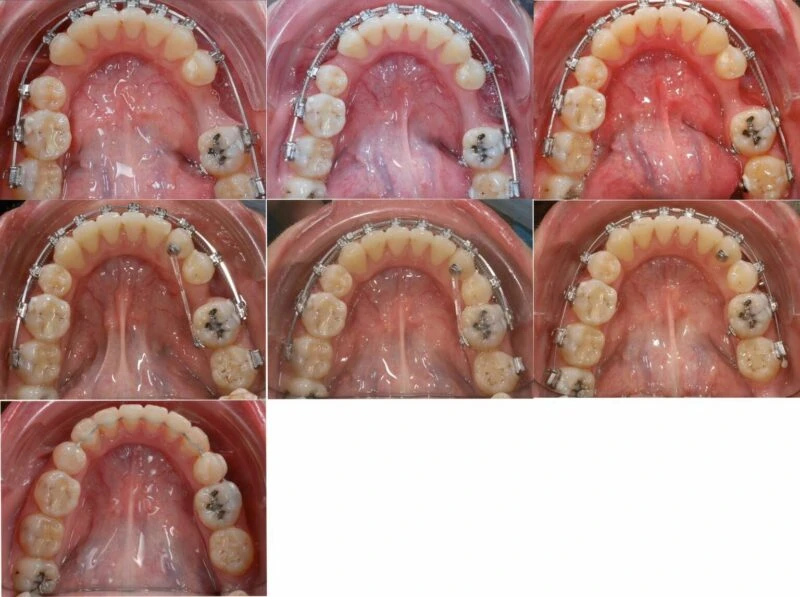

Khí cụ và quá trình điều trị

Hình 9 Ảnh chụp cung răng dưới vào các thời điểm 4, 8, 11, 16, 19, 21, 24 tháng